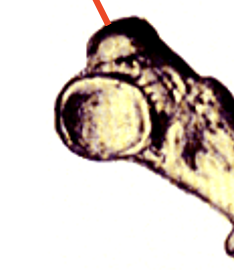

intervertebral foramen

joint between two vertebrae; site where nerves going out to muscles or carrying sensory information into spinal canal emerge

dorsal root ganglia

contain neuronal cell bodies that are involved in carrying sensory information from the periphery to the spinal cord

spinal nerve

the dorsal and ventral roots unite to form this, which continous out to the periphery - contain both sensory and motor information

dorsal horn

dorsal rootlets

dorsal root

transmit sensory information from the periphery to the CNS

ventral horn

ventral rootlets

ventral root

carry motor information from the CNS to the periphery